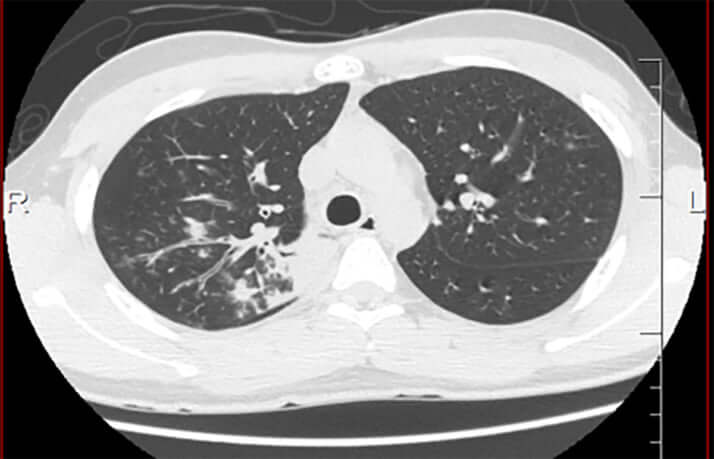

マイコプラズマに感染した患者の体内